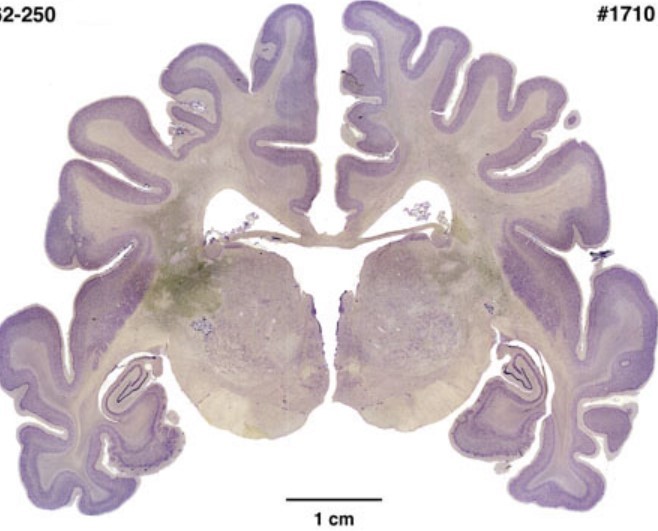

The goal of this course is to introduce a diverse field that is often referred to as “neuroscience”, but has been known by many different names since its birth in the late 1800s. We will survey physiological processes related to behavior and cognition in human and nonhuman species, as well as other biological mechanisms that are relevant to issues in psychology. Topics include basic functional neuroanatomy, neuronal structure and function, & the relationship between brain systems, psychosocial variables, and complex cognitive, perceptual, and emotional processes. We will also discuss neurological, neuropsychological, and psychiatric differences. In addition to serving as a general survey of some of the biological aspects of psychology, this course prepares students for more advanced neuroscience offerings (e.g. Psy 350, Psy 355, Psy 380, Psy 410).